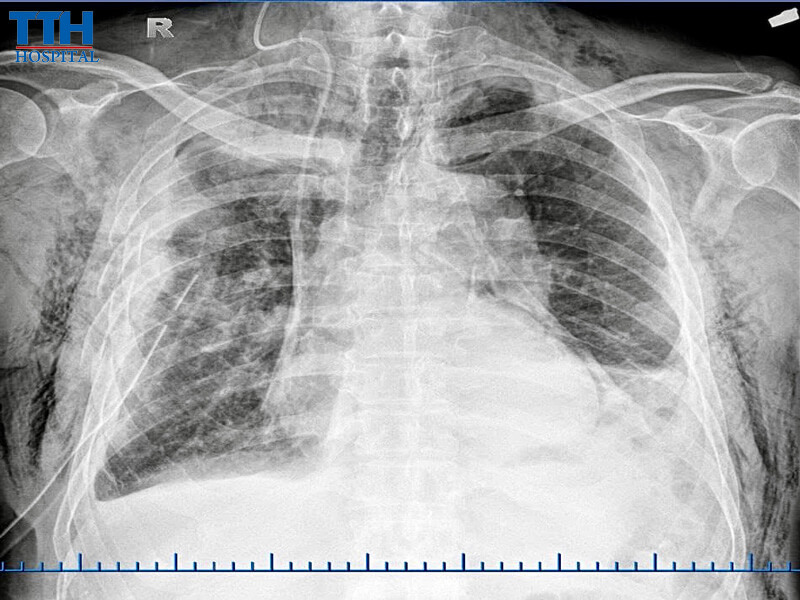

Ngay lập tức, các bác sĩ tiến hành thăm khám kỹ lưỡng và thực hiện các xét nghiệm, chẩn đoán hình ảnh. Kết quả cho thấy:

• Gãy 8 xương sườn cung sau bên phải (từ xương số III đến số X)

• Tràn máu – tràn khí màng phổi lượng nhiều, chèn ép và đẩy lệch trung thất

• Tụ máu thành ngực diện rộng từ nách xuống mào chậu

• Kèm theo suy hô hấp cấp

• Hết đau ngực, hết khó thở, phổi nở tốt khi chụp X-quang